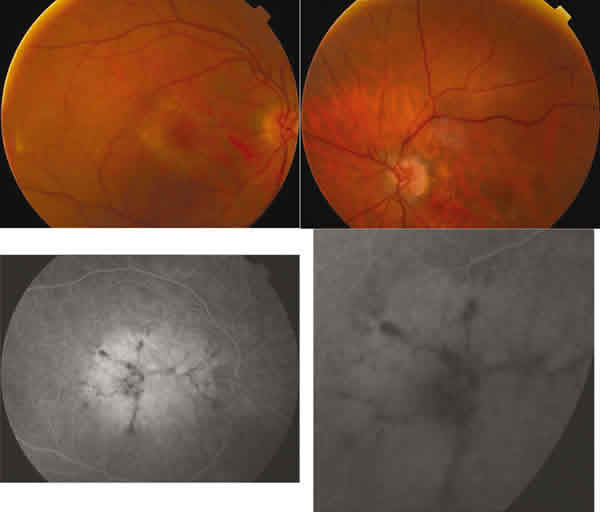

En la AFG presentaba una hiperfluorescencia coroidea macular en el seno de la cual destacaba un patrón radial de líneas hipofluorescentes (figs. 4 y 5). La clasificamos en el grupo II de las distrofias patrón según Gass (patrón tipo mariposa).

Fig. 6. Retinografías y AFG de AO en caso 2. Depósito pigmentario con patrón en mariposa.

Nuestro segundo caso representa la evolución habitual de esta enfermedad, una paciente de 70 años con un progresivo pero lento déficit de AV, confundido en un principio con una DMAE.